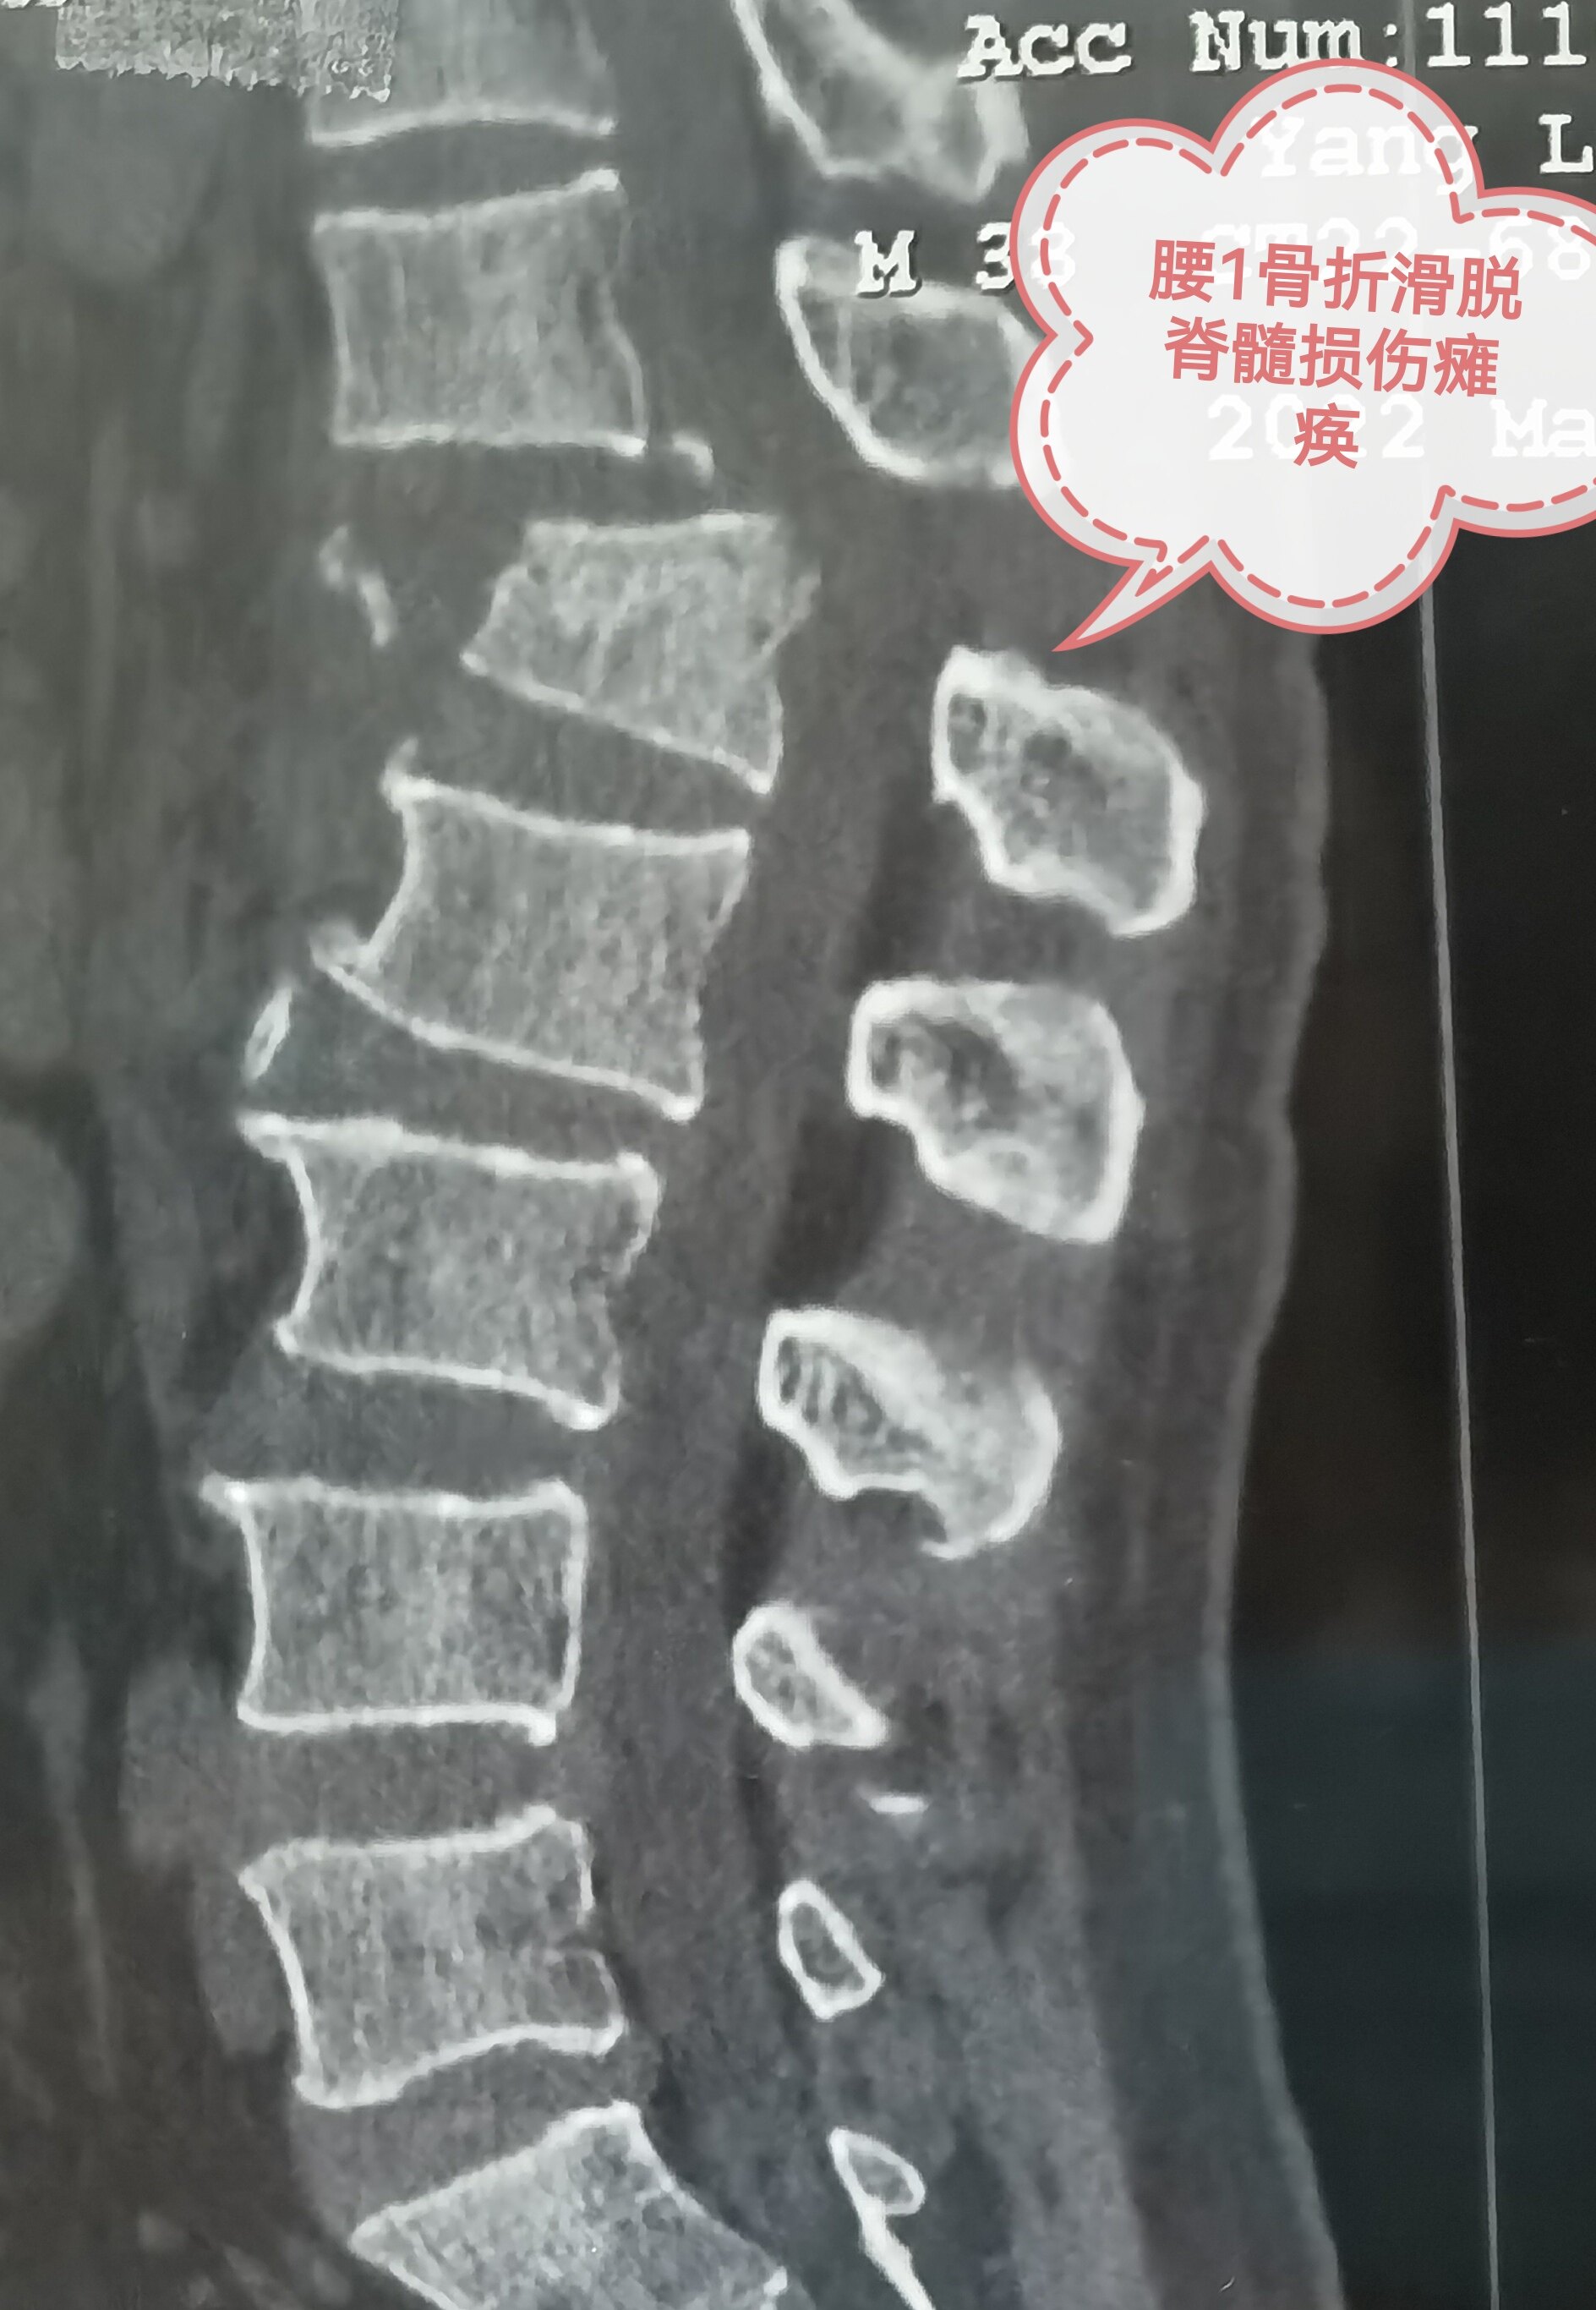

One day, a family member came from the clinic and asked me to consult with my family's films. It turned out that his brother was hit by a heavy object at the age of 38, which immediately caused paralysis of the lower limbs, unconsciousness, and incontinence. He was sent to the local hospital for examination and found that the chest and waist were fractured, the spine slipped, and the spinal cord injury.

Both CT and MRIs before surgery suggest that the chest 12/waist 1 slip. The local hospital urgently performed the internal fixed surgery of the spine reset